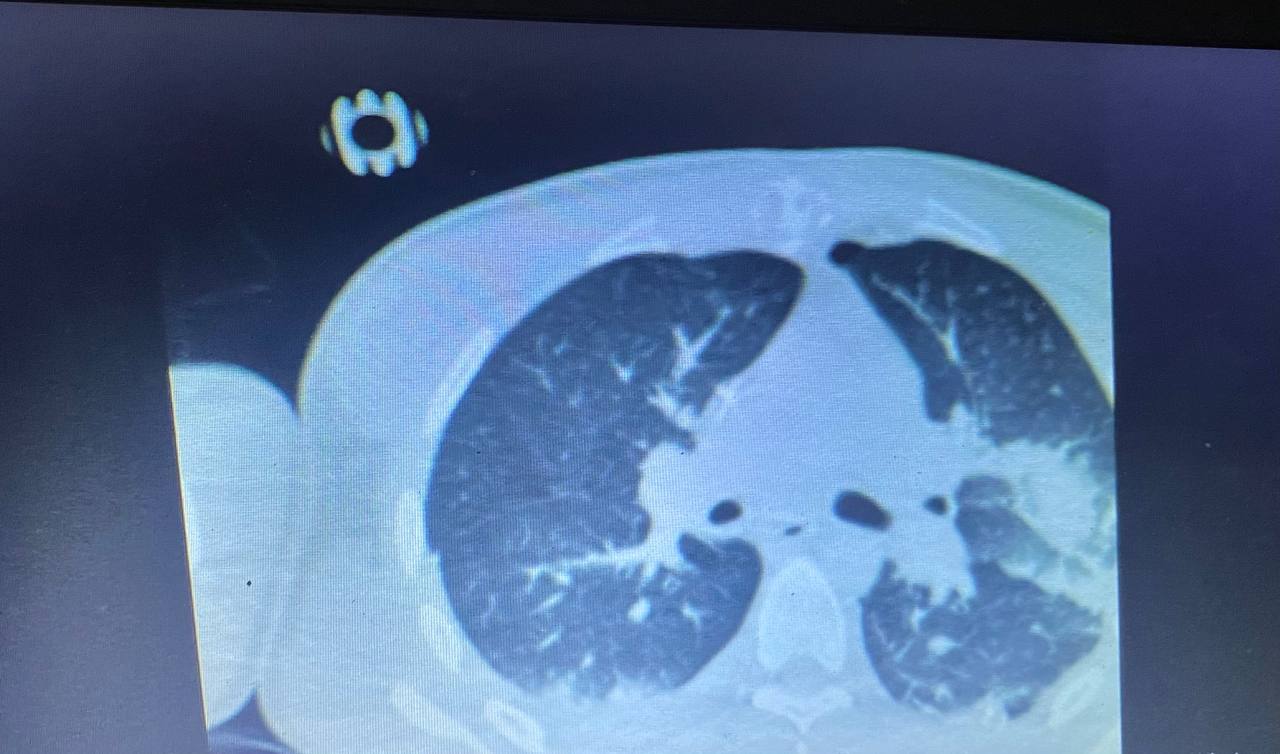

В больнице говорят, что восстанавливаться придется пожизненно. По словам медиков, парень прошел "все нули". Начиная от фронта и до предела жизни. Обломок пробил грудь, разбил грудину, проник в легкие и в желудок.